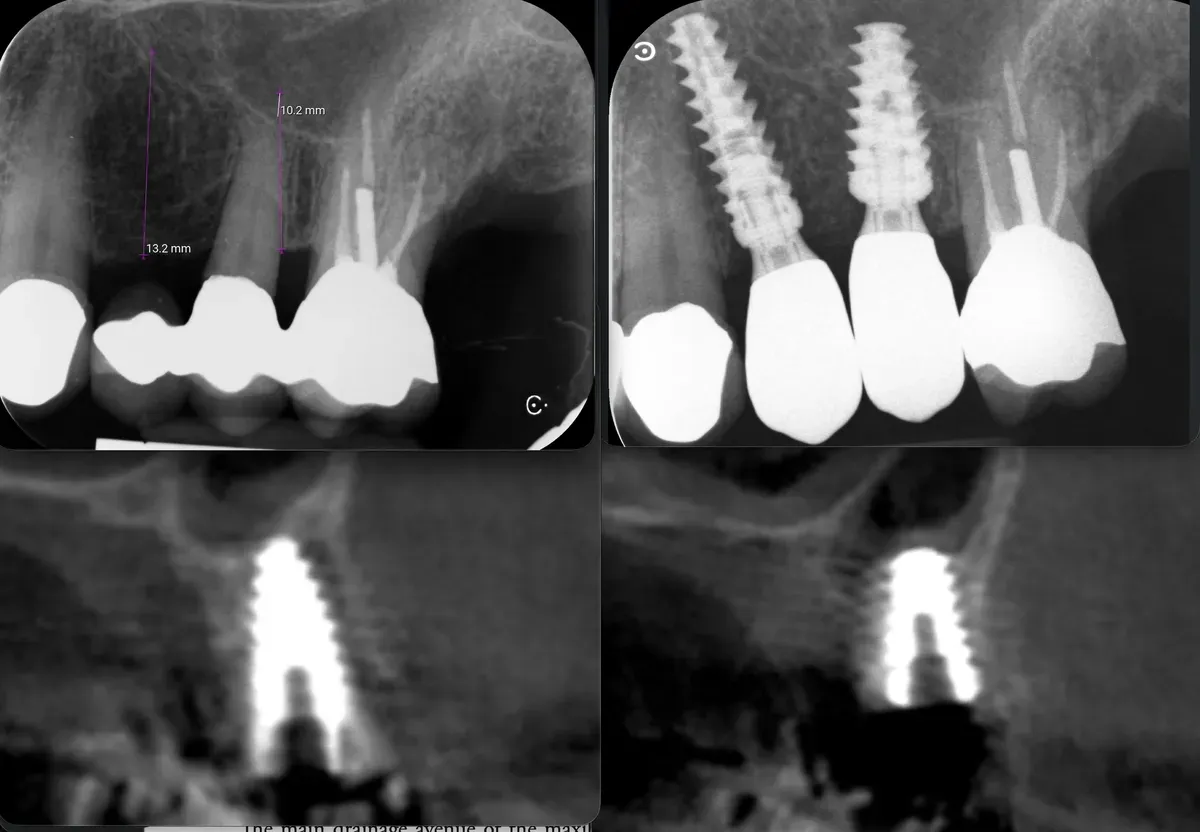

Con gli espansori da 13mm in posizione ho effettuato un controllo radiografico della posizione, prima di procedere ulteriormente.

Strumenti espansori da 13mm in posizione

La CBCT intraoperatoria ha confermato la corretta posizione tridimensionale degli espansori e il raggiungimento della corticale del pavimento del seno in zona 2.5. In caso di dubbi sulla posizione e nel corso di interventi delicati come questo, questo ausilio strumentale è di fondamentale importanza. Ma non è sempre necessaria. L’esposizione, per quanto contenuta, dev’essere sempre ridotta al minimo, compatibilmente con la sicurezza chirurgica.

Visione laterale espansori

Sezione espansore sito 2.4

Sezione espansore sito 2.5

CBCT Post-op: Impianto in posizione 2.4 infracrestale che ha raggiunto la posizione di ingaggio corticale corretta

Espansore in posizione 2.5 con sollevamento della corticale del pavimento del seno

CBCT Post-op: Impianto in posizione 2.5 infracrestale con sollevamento della corticale del pavimento del seno